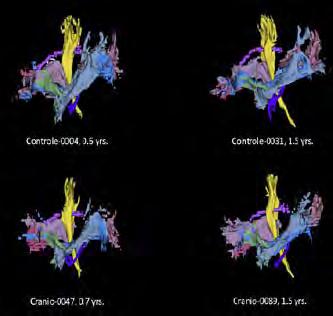

The activities of the MR Physics group are driven by clinical research lines of the Radiology and Nuclear Medicine department such as musculoskeletal research (with Edwin Oei), Lung MRI (with Harm Tiddens and Pier Luigi Ciet) and neuro-oncology (with Marion Smits). Besides the clinical research lines, it is important to notice that several fruitful projects are carried out on technical developments.